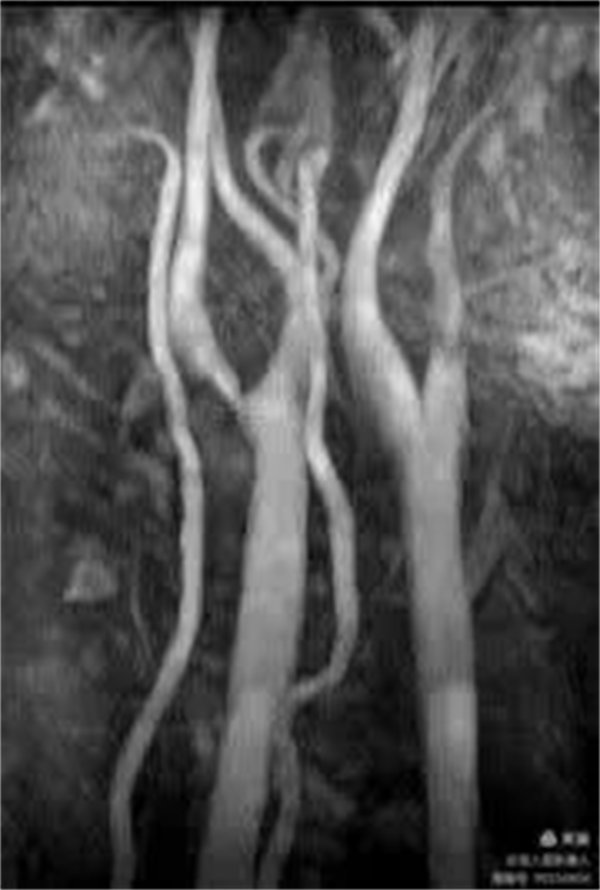

CE-MRA显示颈部血管清晰

血管壁曲面重建显示血管壁,管腔及周围组织结构清晰

CE-MRA主要优势:

1.血管腔的显示比MRA技术更可靠;

2.出现血管狭窄的假象明显减少,狭窄的程度反映比较真实;

3.注射对比剂后血管可显示至4-5级,且血管信号明显增强;

4.一次注射对比剂可完成多部位动脉的显示;

5.动脉瘤不易遗漏;

6.成像速度快。